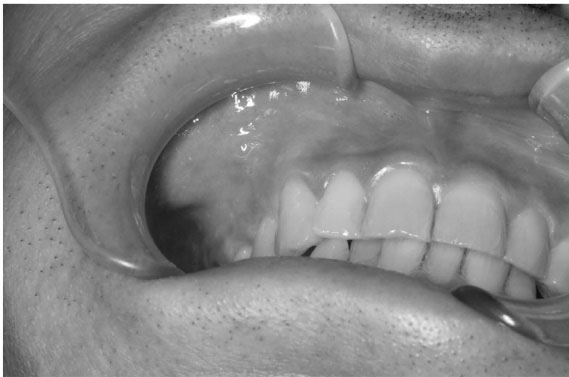

A 47-year-old man visited our hospital with a chief complaint of discomfort and slight intermittent pain in the maxillary gingiva. He had noticed a diffuse swelling in the anterior maxillary area over the past 6 months. On oral examination, a 30 × 25-mm solitary well-defined swelling was seen in the maxillary labial vestibule, extending from the right central incisor to the first molar. The swelling was tender and fluctuant on palpation (). The right maxillary teeth were not mobile and exhibited a vital pulp reaction. The panoramic radiograph revealed a large radiolucent area close to the roots of teeth #12 to #16, extending to the right orbital rim, including two radiopaque structures resembling teeth (). A computed tomographic (CT) examination revealed an oval unilocular radiolucent lesion, approximately 50 × 45 × 35 mm in size with a well-defined border in the right maxilla and including two supernumerary teeth ().

Figure 1. Intraoral photograph in the initial visit showing swelling in the vestibule